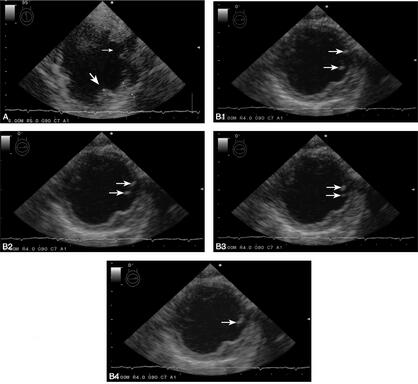

1小时条评论1 病例简介 患者男,74岁。因头晕、视物不清1日于2009年5月28日入院。患者于入院前一天在行走中突然感到头晕、视物不清,无头痛、恶心、呕吐及其他不适,次日到当地医院就诊,检查发现左眼视野中心暗点,颅脑MRI:双侧大脑后动脉和大脑中动脉供血区散在新鲜梗死灶...